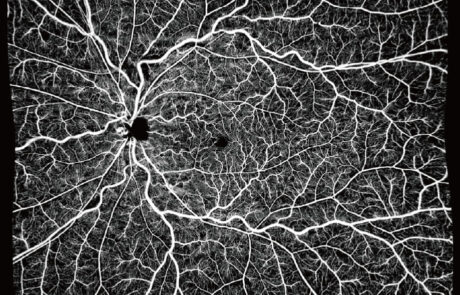

YAlkaid

100KHz Widefield

Full-Range SS-OCT

Das TowardPi 100-kHz-Breitband-Vollbereichs-SS-OCTA basiert auf vollständig eigenentwickelten Kernkomponenten und vereint hohe Scan-Tiefe mit exzellenter Auflösung in kurzer Erfassungszeit.

Es ermöglicht hochwertige OCT-Angiographie des vorderen und hinteren Augenabschnitts und liefert zuverlässige, detaillierte Bilddaten.

Intelligente Software mit Choroid-OCTA-Algorithmen, Flussquantifizierung, iSpot-Funktion sowie Analyse von Netzhautkrümmung und Gefäßdichte erweitert die diagnostischen Möglichkeiten und unterstützt ein modernes, präzises Krankheitsmanagement.

Klinische Bilder